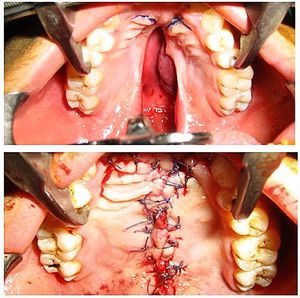

Very nice tissue graft and closure by an excellent surgeon!π€π€